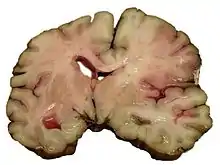

Intracerebral hemorrhage

It generally occurs in small arteries or arterioles and is commonly due to hypertension,[52] intracranial vascular malformations (including cavernous angiomas or arteriovenous malformations), cerebral amyloid angiopathy, or infarcts into which secondary hemorrhage has occurred.[2] Other potential causes are trauma, bleeding disorders, amyloid angiopathy, illicit drug use (e.g., amphetamines or cocaine). The hematoma enlarges until pressure from surrounding tissue limits its growth, or until it decompresses by emptying into the ventricular system, CSF or the pial surface. A third of intracerebral bleed is into the brain's ventricles. ICH has a mortality rate of 44 percent after 30 days, higher than ischemic stroke or subarachnoid hemorrhage (which technically may also be classified as a type of stroke[2]).

Hemorrhagic

Hemorrhagic stroke is classified based on their underlying pathology. Some causes of hemorrhagic stroke are hypertensive hemorrhage, ruptured aneurysm, ruptured AV fistula, transformation of prior ischemic infarction, and drug-induced bleeding.[66] They result in tissue injury by causing compression of tissue from an expanding hematoma or hematomas. In addition, the pressure may lead to a loss of blood supply to affected tissue with resulting infarction, and the blood released by brain hemorrhage appears to have direct toxic effects on brain tissue and vasculature.[46][67] Inflammation contributes to the secondary brain injury after hemorrhage.[67]